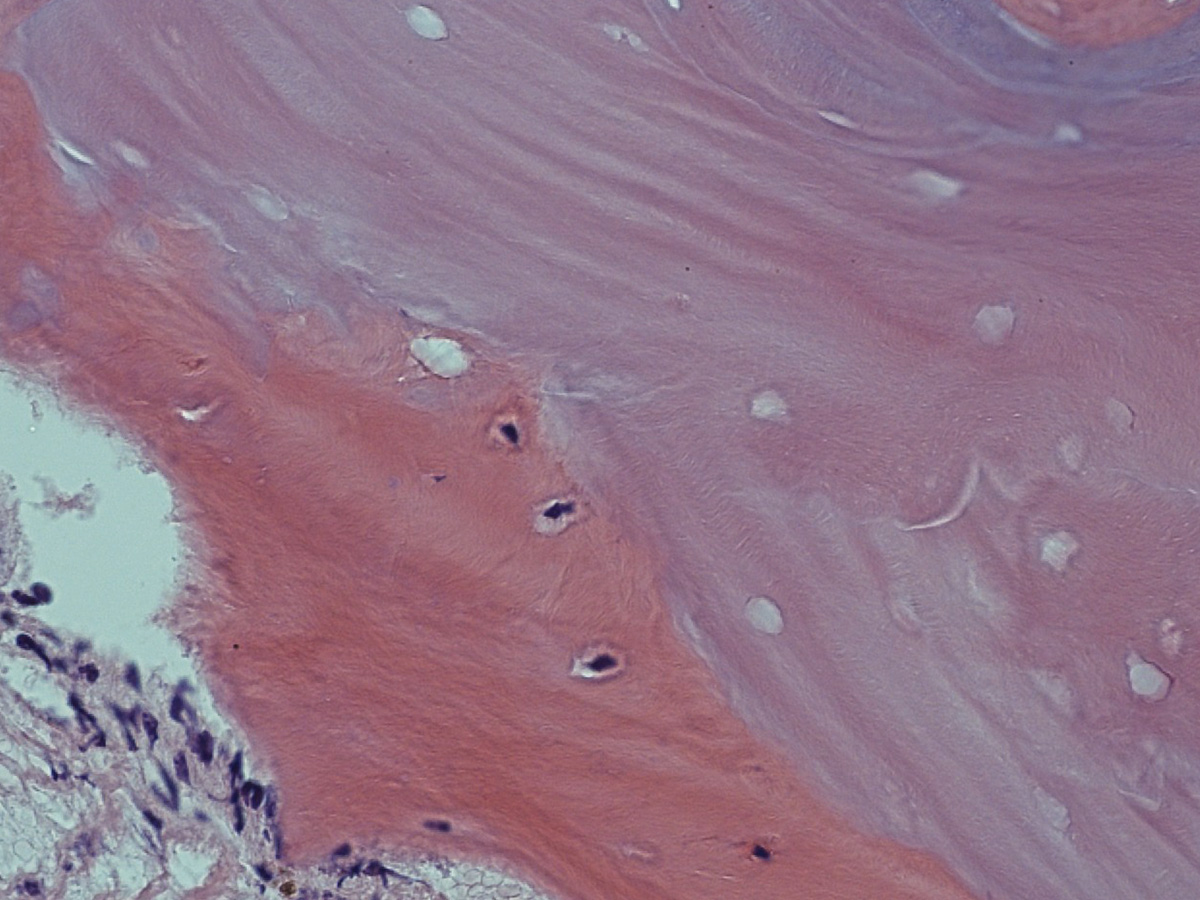

Abbildung 9

Biopsate aus der Maxilla, Entnahme nach vier Monaten.

Abbildung 11

Histologie bei stärkerer Vergrößerung: In den Resorptionslakunen sind Osteozyten erkennbar.